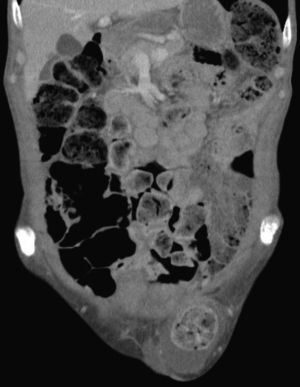

Tras la valoración por cirugía se decide pedir una TC abdominal que es informada como: «Múltiples quistes simples distribuidos en ambos lóbulos hepáticos. Marco cólico en su totalidad ocupado por heces, hernia inguinal izquierda que contiene segmento corto del sigma. Calcificación de aorta infrarrenal y ambas arterias ilíacas, alteración de la trabeculación en acetábulo y pala ilíaca del lado izquierdo» (figs. 1 y 2).

Tras las pruebas complementarias se llegó al diagnóstico definitivo de hernia inguinal incarcerada, con lo que se procedió a efectuar el tratamiento quirúrgico definitivo con carácter de urgencia. Tras la cirugía el paciente evolucionó favorablemente y le fue dada el alta con control ambulatorio. Durante el seguimiento desde la consulta de atención primaria el paciente tuvo buena evolución clínica.